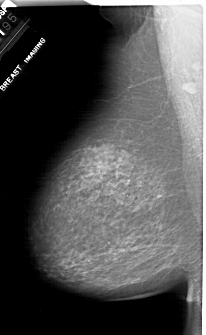

A_1917_1.RIGHT_MLO

RIGHT_MLO LINES 6871 PIXELS_PER_LINE 4066 BITS_PER_PIXEL 12 RESOLUTION 43.5 OVERLAY